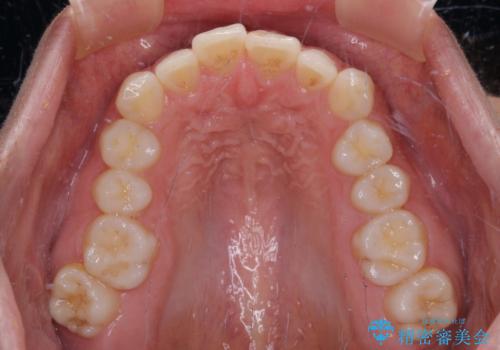

【モニター】突出した前歯 補助装置を併用したインビザライン矯正

- 上下前歯が非接触となり、前方に突出していることを気にして来院された患者様です。

咬合力が強く、全体的に歯がすり減っているため、インビザライン単独での上顎歯列移動は困難と判断し、補助装置により上顎歯列を後方移動させ、その後インビザラインにて仕上げていくこととしました。

補助装置なしでも改善できる可能性はありましたが、補助装置で確実性を上げ、短期間できっちりと仕上げることができました。